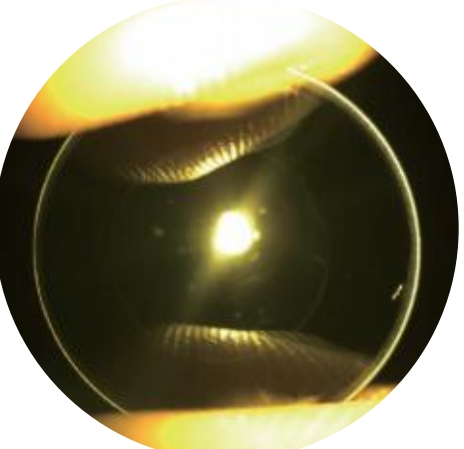

角膜塑形镜(OK镜)

角膜塑形镜是一种特殊设计的隐形眼镜。与隐形眼镜不同,角膜塑形镜不是在白天配戴以看清物体,而是在晚上睡觉时配戴,通过轻微改变角膜的形状来达到白天不近视的效果。